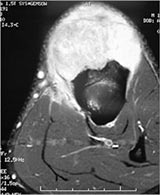

MRI:

- Mass on surface of bone

- Intermediate signal on T1 weighted images and high signal on T2 consistent with cartilage

- Usually no intramedullary invasion but may see slight erosion or saucerization of cortex

- Periosteal reaction evident on MRI as very low signal on T1 and T2 weighted images